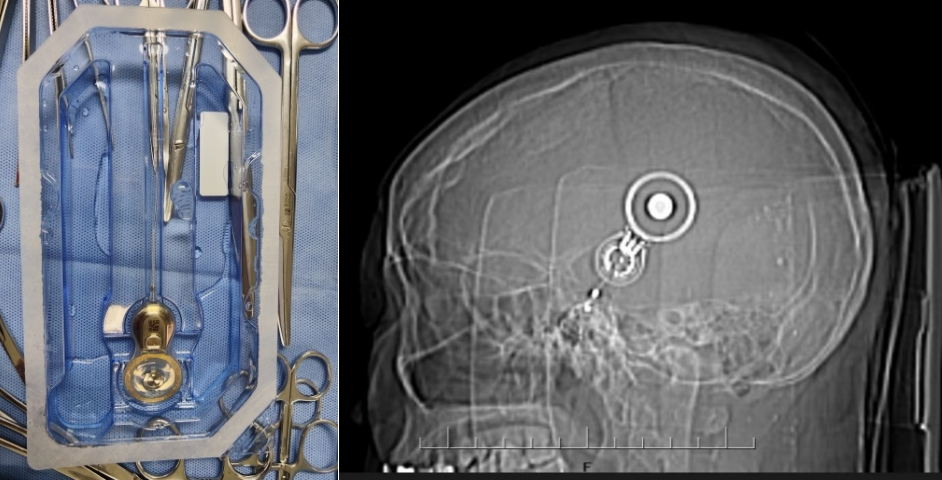

入院后,华人色情 耳鼻咽喉科专家团队对徐某进行了全面细致的检查和评估,结合他的具体情况,制定了个性化的手术方案。手术过程顺利,成功将集采的人工耳蜗植入徐某耳内,术中神经电生理监测,耳蜗电极均正常工作,术后耳蜗CT显示电极位置正确。术后,经过医护人员精心护理和康复指导,徐某恢复良好,各项指标正常,顺利出院。主刀医生白忠主任叮嘱患者,1个月后返院,人工耳蜗开机后,患者就可以听到声音了,恢复有声世界。

据华人色情 耳鼻咽喉科专家白忠主任医师介绍,人工耳蜗是一种电子装置,通过植入体内的电极系统直接刺激听神经,帮助重度、极重度感音神经性耳聋患者恢复听力。以往,人工耳蜗价格高昂,让许多患者望而却步。此次国家集采政策落地云南后,人工耳蜗价格大幅下降,极大减轻了患者的经济负担,让更多听障患者有机会接受治疗,重获听力。